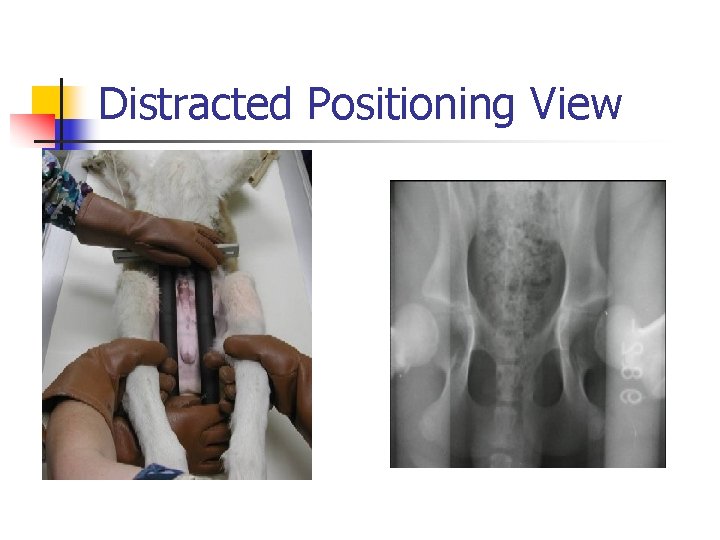

Distracted or Penn. HIP method n n Refers to a specific diagnostic technique of hip laxity information. More reliable indication of hip laxity than extended view. Stress radiographic procedure with 3 views (compression, standard extended, and distraction view). To perform this method, veterinarian or technician must be certified.

Distracted Positioning View